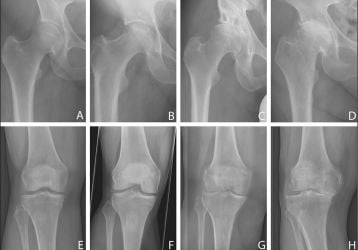

Диета при заболеваниях коленных и тазобедренных суставов: принципы здорового питания

Принципы питания при заболеваниях суставов крупных суставов нижних конечностей(тазобедренных и коленных). Полезные и запрещенные продукты.